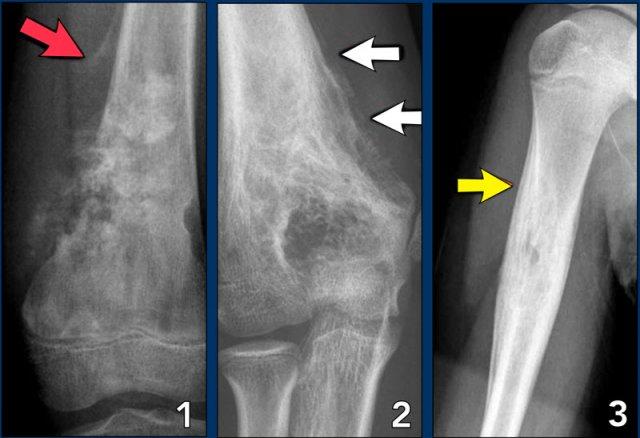

Aggressive periosteal reaction (2)

- Ung thư xương (Osteosarcoma) với phản ứng màng xương gián đoạn và tam giác Codman ở phần gần (mũi tên đỏ).

Có sự hình thành xương màng xương vuông góc với xương vỏ và sự hình thành chất nền xương lan rộng do chính khối u tạo ra. - Ewing sarcoma với phản ứng màng xương dạng lớp mỏng và gián đoạn khu trú. (mũi tên trắng)

- Nhiễm trùng với phản ứng màng xương nhiều lớp.

Lưu ý rằng viêm màng xương có tính chất xâm lấn, nhưng không xâm lấn như trong hai trường hợp còn lại.